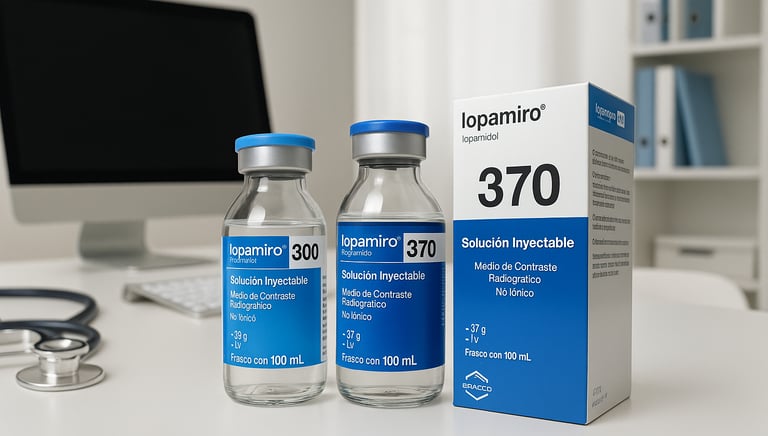

Inyector automatizado que administra medios de contraste en estudios de tomografía computarizada (TC).

Innovación en medios de contraste para mejores resultados

Jeringa estéril diseñada para inyectores automáticos de medios de contraste en estudios de imagenología